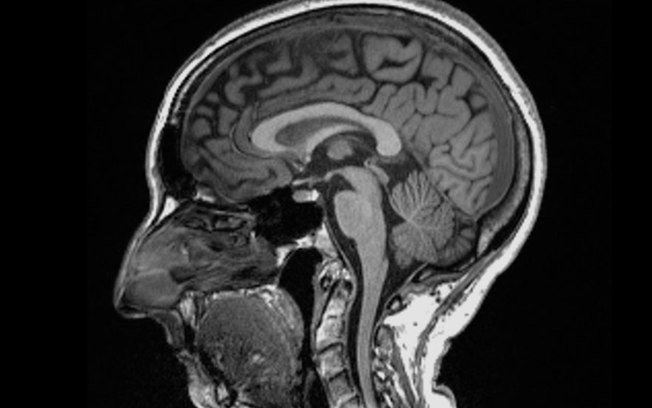

Pegar covid-19 pode causar alterações no cérebro, sugere um estudo publicado na revista científica Nature .

Cientistas encontraram diferenças significativas em exames de ressonância magnética realizados em pacientes antes e depois da infecção.

Mesmo após uma infecção leve, o tamanho geral do cérebro havia encolhido um pouco, com menos massa cinzenta nas partes relacionadas ao olfato e à memória.

– O tamanho geral do cérebro em participantes infectados havia encolhido entre 0,2 e 2%;

– Houve perdas de massa cinzenta nas áreas olfativas e regiões ligadas à memória;